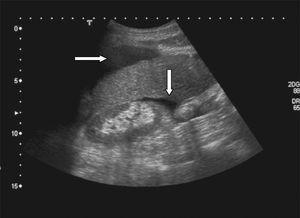

Ante la presencia de un cuadro de dolor abdominal con signos de inestabilidad hemodinámica se realizó ecografía abdominal urgente, en la que se observó abundante líquido libre peritoneal (fig. 1); posteriormente, y tras estabilizar a la paciente, se realizó TAC abdominal urgente en la que se observó línea de rotura esplénica intraparenquimatosa (fig. 2).

Figura 2. Tomografía axial computarizada abdominal: línea de rotura esplénica.

Sin embargo, una vez estabilizado el paciente, la TAC abdominal es el método de elección, ya que permite visualizar el tipo y la magnitud de la lesión esplénica7.